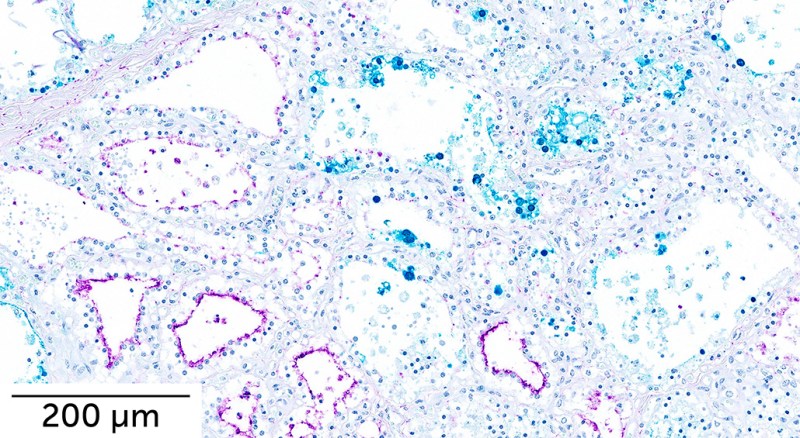

An H5N1 virus isolated from an infected cow spread to the mammary glands of mice and some ferrets — common stand-ins to study flu infections in humans — exposed to the virus directly in their noses, virologist Amie Eisfeld of the University of Wisconsin–Madison and colleagues report July 8 in Nature. A bird flu virus taken from an infected person in 2004 also made it to the mouse and ferret mammary glands. But additional experiments show that the virus isn’t very effective at spreading through the air.

The new study finds that the H5N1 virus currently circulating in U.S. cows also charts a path to mammary glands, suggesting that the tissue unique to mammals is a more common target for the virus than originally thought.

The virus has been detected in cow milk (SN: 4/25/24). The surface of cows’ mammary cells is covered in a ducklike protein that the bird flu virus can exploit to gain entry, researchers report in the July Emerging Infectious Diseases. Such infections might explain how the virus is spreading among cattle. It’s possible that contaminated milking equipment could carry virus from one cow’s udders to another, a separate group of researchers reported in the August Emerging Infectious Diseases.

In mice and ferrets, the virus spread to the lungs, as well as throughout the body to organs including the brain, intestines, kidney and heart. The virus also spread to the mammary glands of mice and some ferrets.